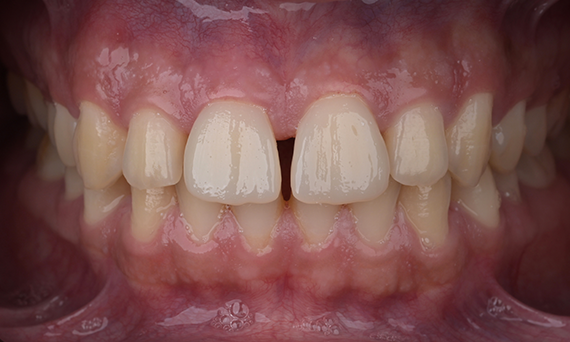

Réhabilitation esthétique d’une amélogenèse imparfaite

CEREC Tessera

Une restauration esthétique dans la région antérieure a pu être réalisée avec des restaurations CEREC Tessera en laboratoire, facettes en Celtra Ceram .

Avant : l’objectif du traitement était de réhabiliter le maxillaire antérieur et la mandibule pour une amélioration esthétique. Le diagnostic clinique a révélé une ameloenesis imperfecta.

Après : restauration fabriquée en laboratoire à partir de la céramique avancée au disilicate de lithium CEREC Tessera et, pour un résultat esthétique élevé, facettes en Celtra Ceram.

Sabine Mayer (CDT)

Coblence, Allemagne

Mario Pace (CDT)

Lahnstein, Allemagne